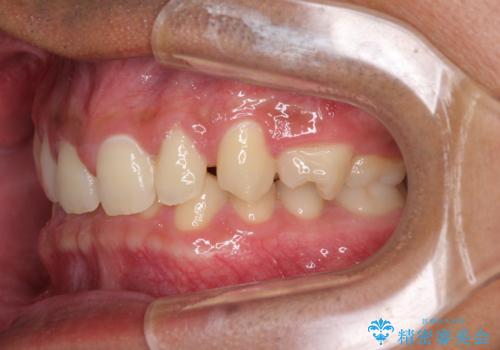

著しいディープバイトと隙間だらけの歯列

- 歯のデコボコと歯の隙間を気にして来院された患者様です。

隙間の原因は、埋伏や前後に重なってしまっている上顎小臼歯と、下の前歯が見えなくなるくらいのディープバイトで、それらを改善する必要がありました。